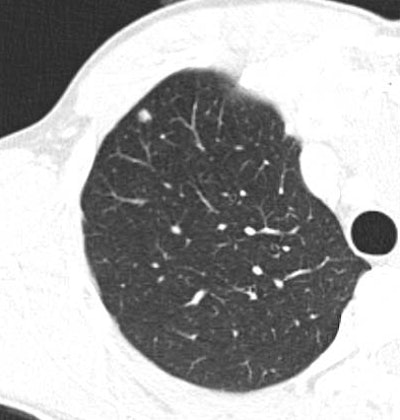

| Above, false-positive lesion detected by ICAD-L was actually mucus in bronchus. Below, true negative nodule detected by the reader and ICAD-L. Images courtesy of Dr. Peter Herzog. |